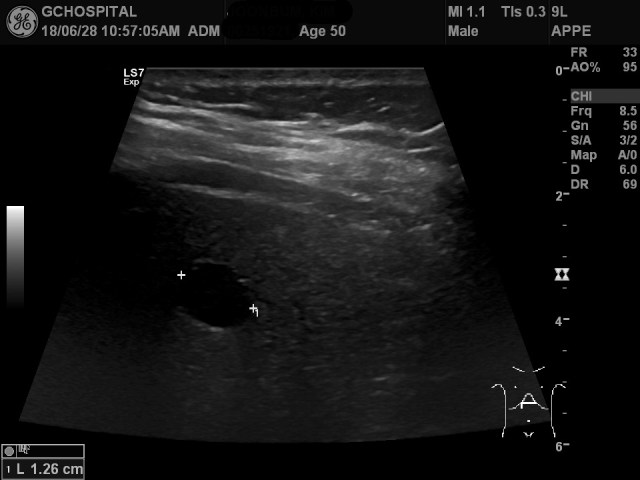

검진 목적으로 내원한 50세 남자환자의 초음파영상입니다. 간 좌엽을 횡단면으로 스캔한 영상인데, 별다른 병변이 전혀 안보이는 중에 무언가 희미한 그림자가 살짝 지나가는것 같아, 해당 부위에 포커스를 맞추고 아무리 다른 파라미터들을 맞춰봐도 병변이 있는것처럼 보이지 않는겁니다. 그럼에도 불구하고, 희미한 그림자 자체는 특정한 위치에서 계속 기척이 보여서 해당 부위를 표시했는데, 위 영상처럼 그 부위에 무언가가 있다는 느낌은 전혀 들지 않습니다.